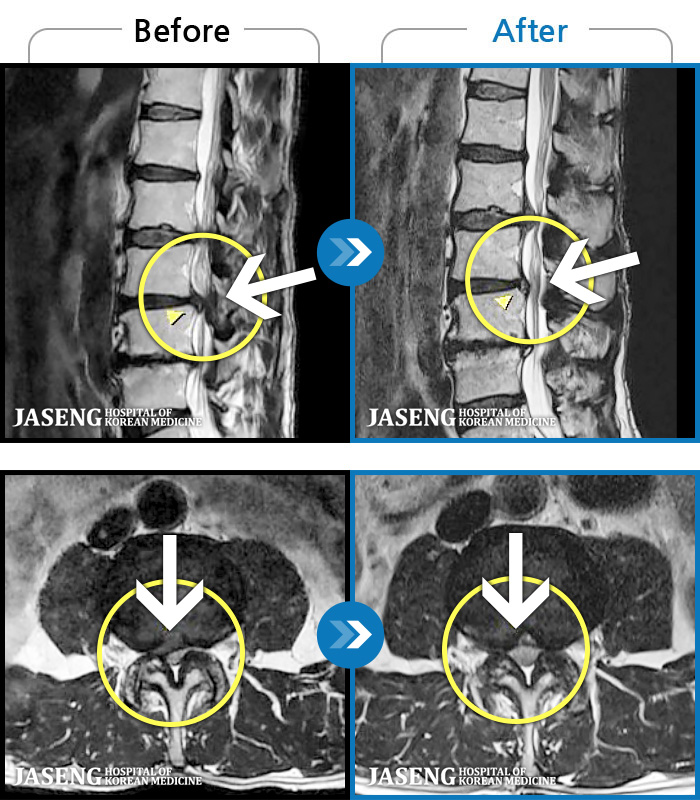

허리디스크

광주 · 장영우 원장

양측 허리부터 골반 묵직한 통증, 좌측 다리 외측까지 이어지는 당기는 통증으로 내원하셨습니다.

촬영시기

2503.04.01 ~ 2509.11.01

2025.09.22